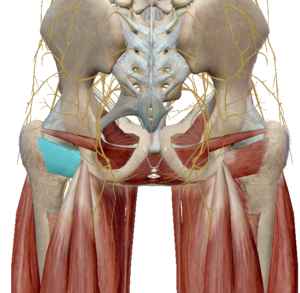

(10) 치골근

치골근은 이름 처럼 치골에서 대퇴골로 연결된 근육입니다.

수축 시 고관절 굴곡과 내전, 내회전이 발생합니다.

(11) 박근

박근은 치골에서 슬관절 내측으로 연결된 근육입니다.

수축 시 고관절 굴곡과 내전, 내회전이 발생합니다.